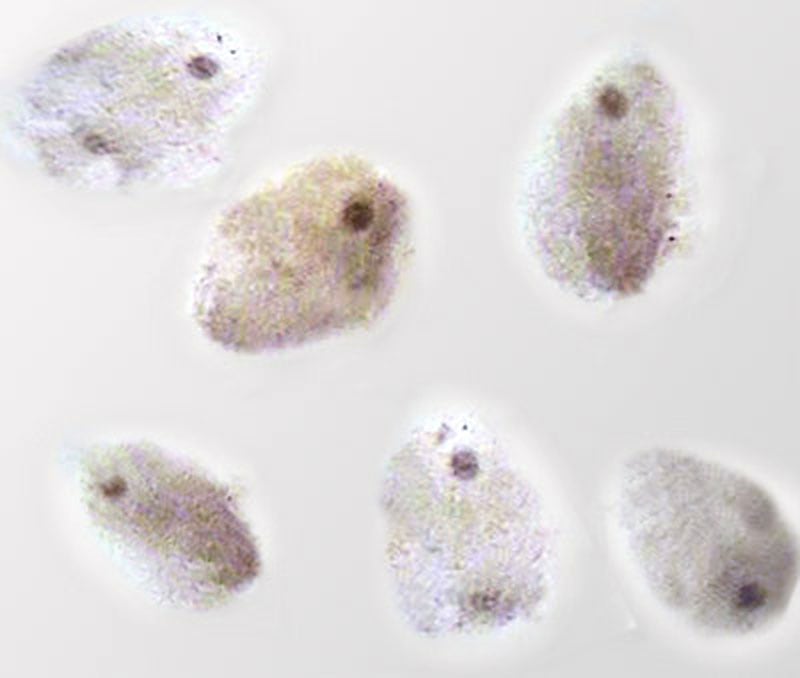

Die Eizellen werden im Labor in Nährlösung gegeben und mit ca. 50.-100.00 gut beweglichen Spermien überschichtet. Die Schälchen werden dann über Nacht im Brutschrank „inkubiert“ ( kultiviert).

Nachdem 19-21 Stunden später festgestellt wurde, wie viele Eizellen das so genannte Vorkernstadium (PN Stadium-Pro Nucleus) erreicht haben, muß (zumindest in Deutschland) ausgewählt werden, welche PN-Stadien Zellen (max. 3) den Befruchtungsvorgang abschließen soll. Die Vorkerne enthalten jeweils die Chromosomen der Eizelle und der Samenzelle.